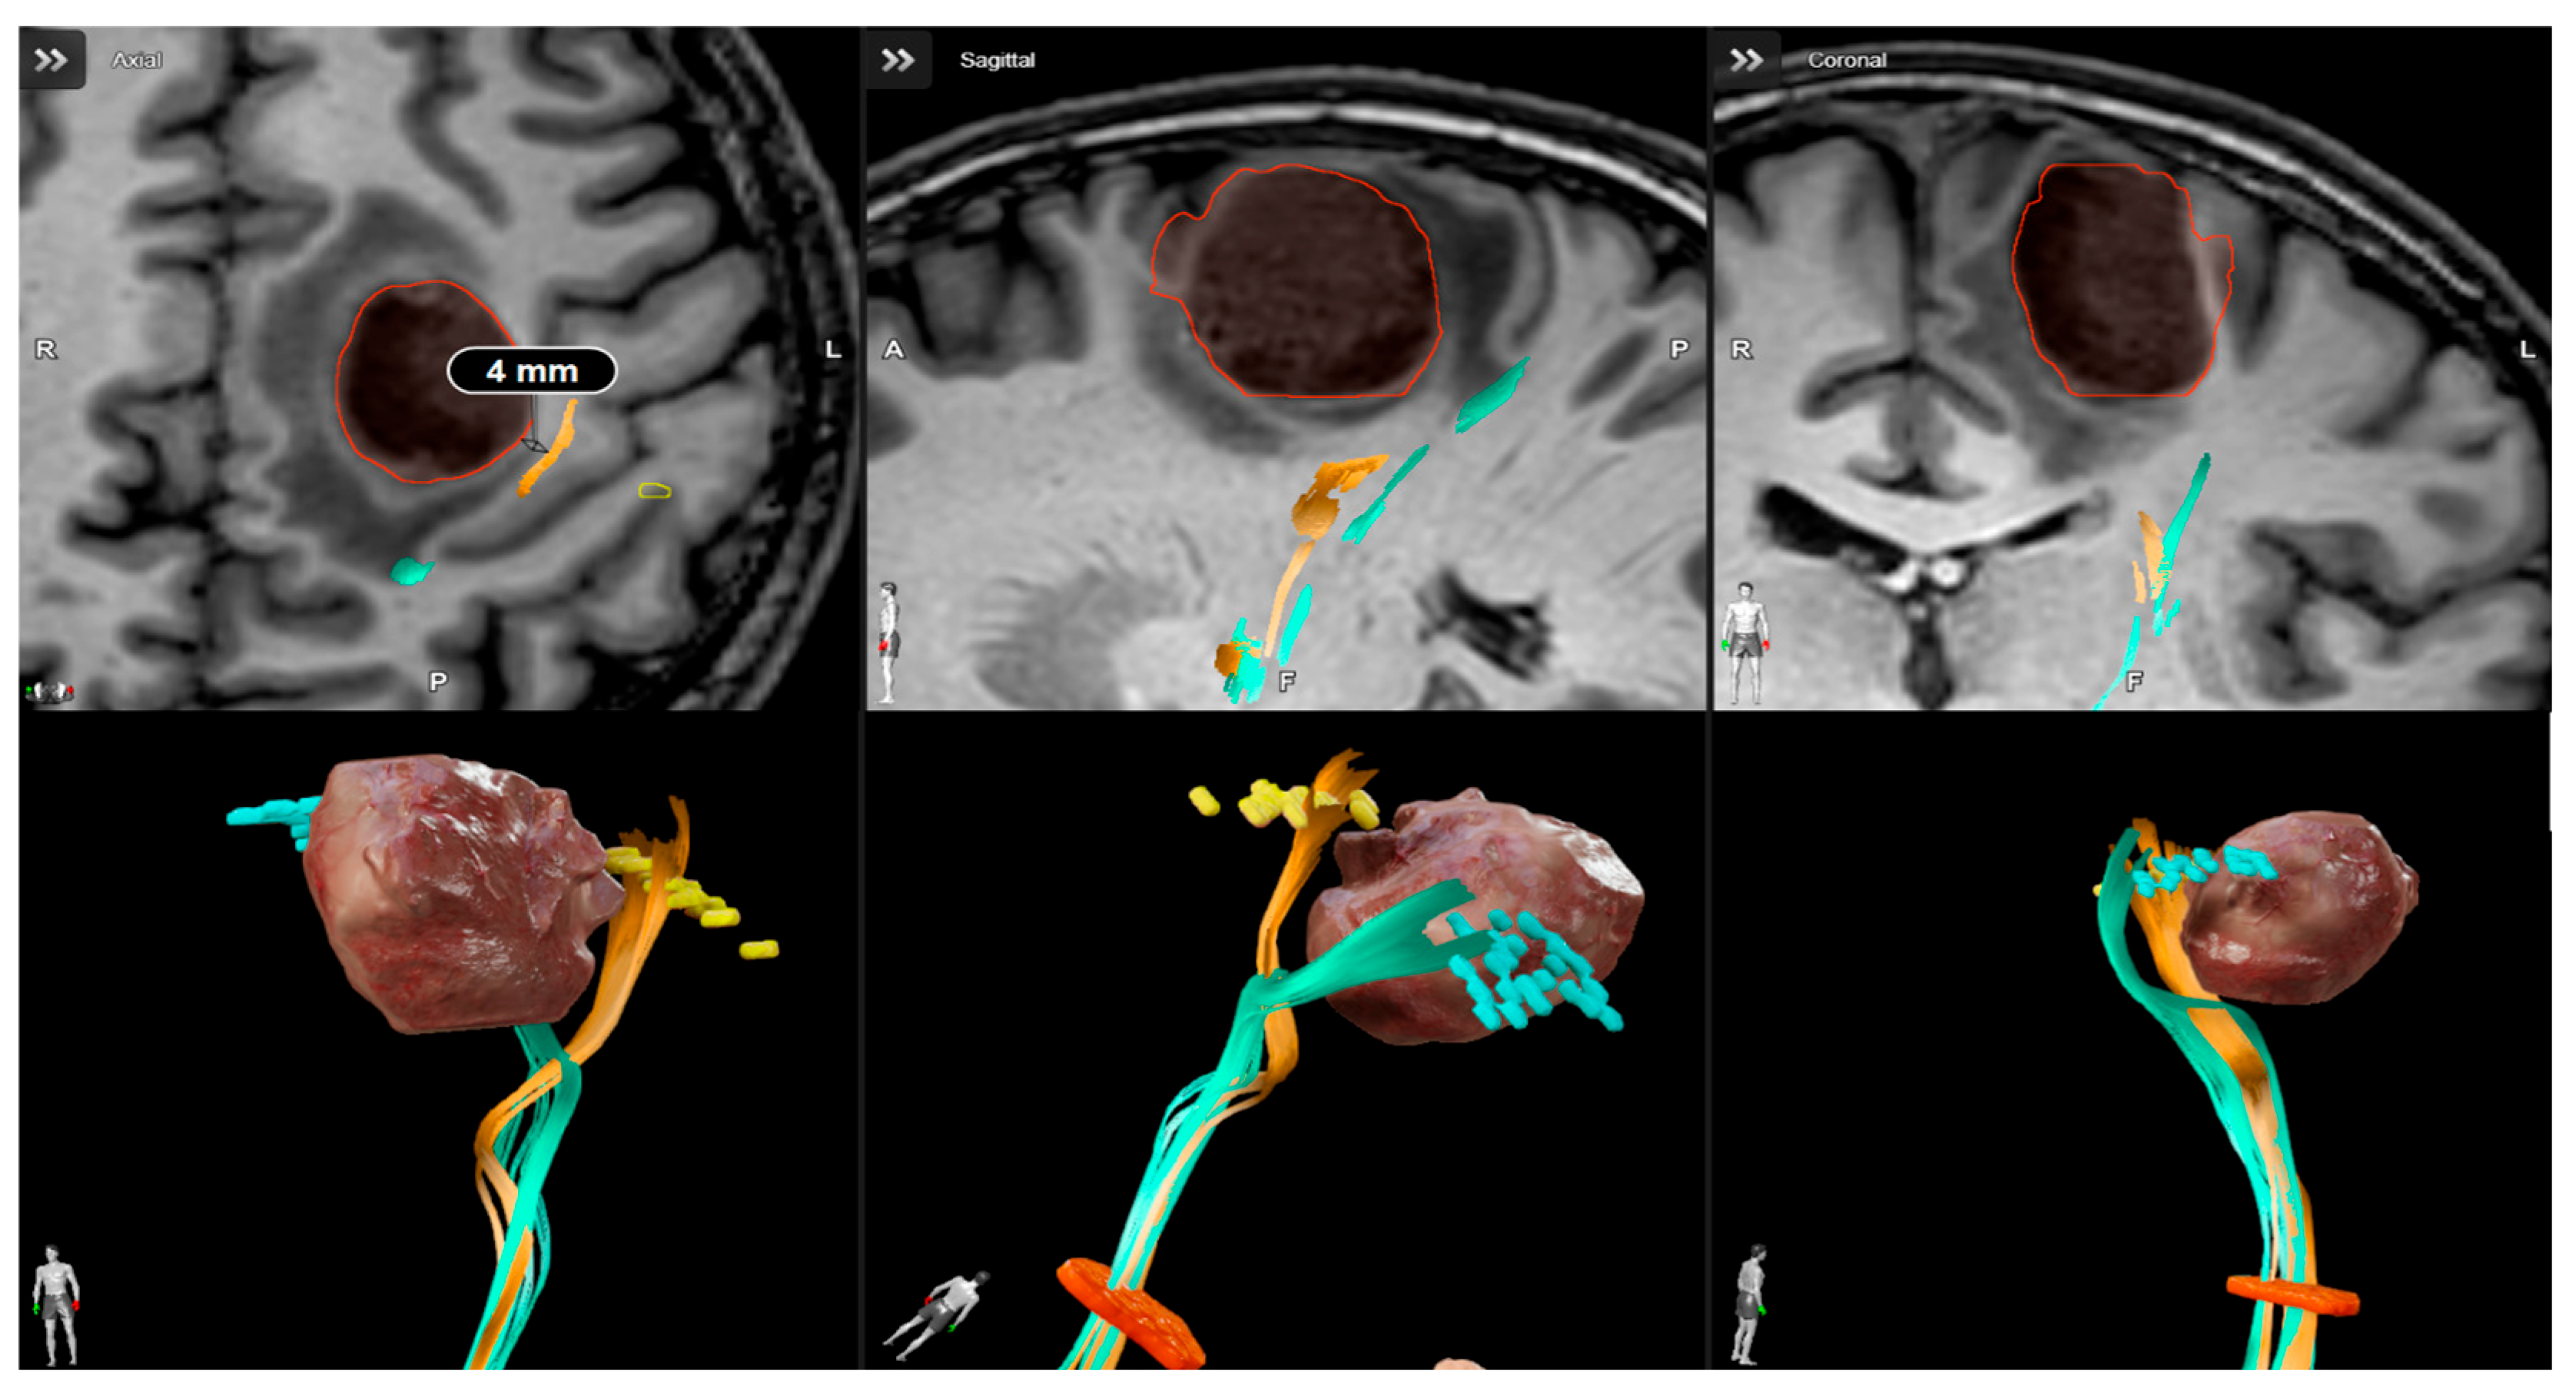

- Conti, A.; Raffa, G.; Granata, F.; Rizzo, V.; Germanò, A.; Tomasello, F. Navigated Transcranial Magnetic Stimulation for “Somatotopic” Tractography of the Corticospinal Tract. Neurosurgery 2014, 10 (Suppl. 4), 542–554. [Google Scholar] [CrossRef]